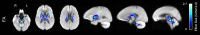

Aging is associated with widespread alterations in cerebral white matter (WM). Most prior studies of age differences in WM have used diffusion tensor imaging (DTI), but typical DTI metrics (e.g., fractional anisotropy; FA) can reflect multiple neurobiological features, making interpretation challenging. Here, we used fixel-based analysis (FBA) to investigate age-related WM differences observed using DTI in a sample of 45 older and 25 younger healthy adults. Age-related FA differences were widespread but were strongly associated with differences in multi-fiber complexity (CX), suggesting that they reflected differences in crossing fibers in addition to structural differences in individual fiber segments. FBA also revealed a frontolimbic locus of age-related effects and provided insights into distinct microstructural changes underlying them. Specifically, age differences in fiber density were prominent in fornix, bilateral anterior internal capsule, forceps minor, body of the corpus callosum, and corticospinal tract, while age differences in fiber cross section were largest in cingulum bundle and forceps minor. These results provide novel insights into specific structural differences underlying major WM differences associated with aging.